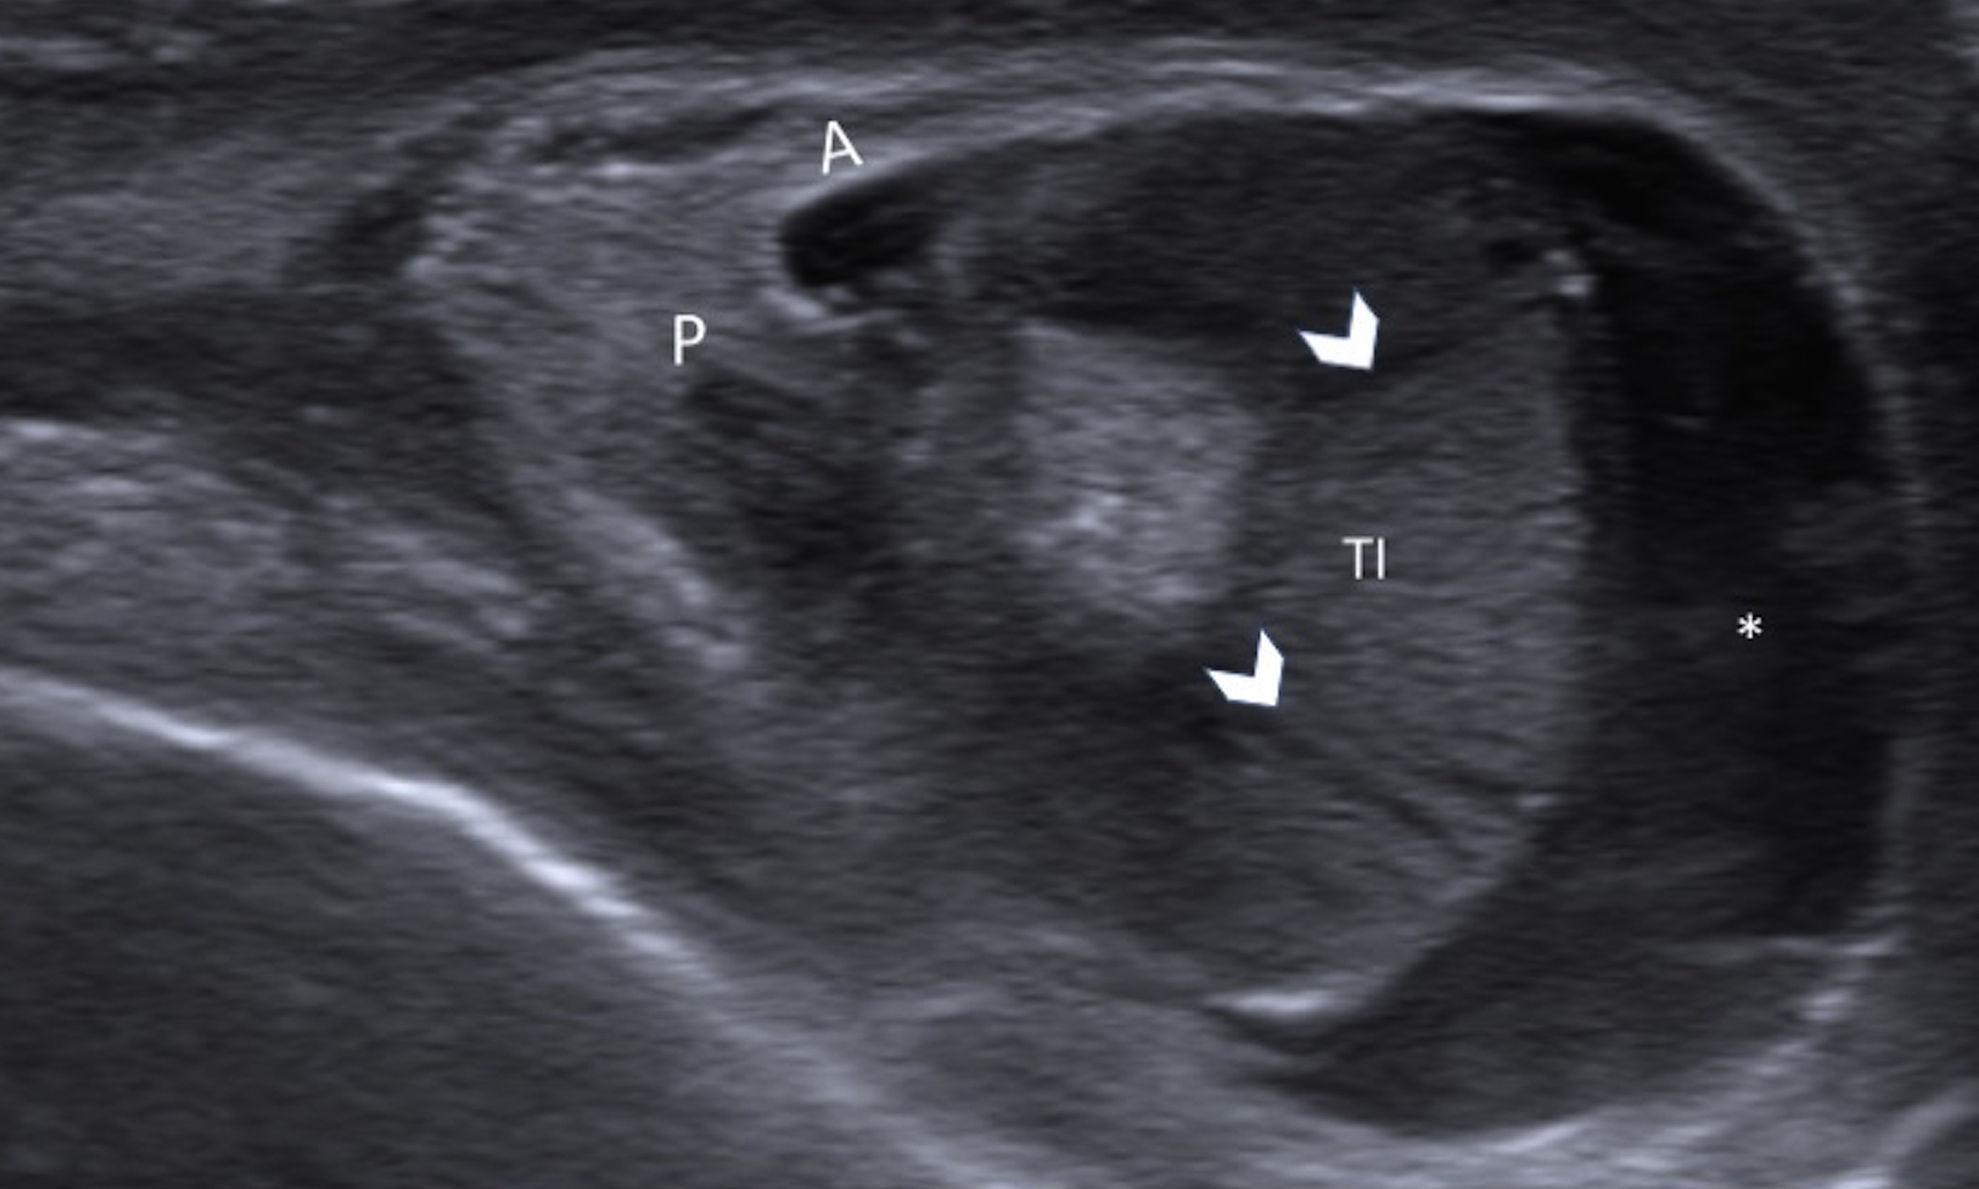

Newborn with an enlarged and firm left testis Pediatric Radiology Testicular Torsion In Newborn The sonographic spectrum we describe should allow one to easily differentiate neonatal testicular torsion. Neonatal testicular torsion is a rare event in clinical practice. Newborn torsion, which accounts for 12 percent of all cases of testicular torsion, is usually discovered after the development of an. In neonates the attachment between the scrotum and tunica vaginalis is not fully formed and. Testicular Torsion In Newborn.

Ultrasonography of Extravaginal Testicular Torsion in Neonates Testicular Torsion In Newborn A hard firm testis with bluish discolouration of the scrotum in the. The presence of a testicular mass or swelling in a neonate can be a dilemma. In neonates the attachment between the scrotum and tunica vaginalis is not fully formed and the. In testicular torsion, twisting of the testis around its vascular. Neonatal testicular torsion is rare, but can. Testicular Torsion In Newborn.